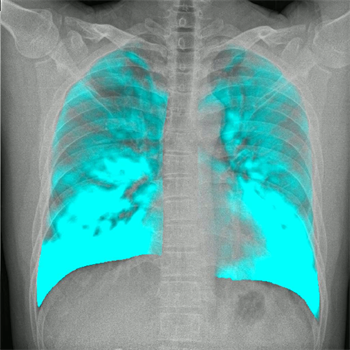

影像动态化可谓是近年来临床最火热的研究方向之一,与常规的静态平片不同的是,这项技术让临床平片“动”起来,但不仅仅只是“动”起来。在一个时间单位内低剂量高速获取多帧X线影像,得到连续动态摄影图像,看动态图像,不仅仅是看的更“准”一点,更多的是,影像诊断方式,向功能化上更进了一步。

能够最直观体会到动态DR直接的优势是,规避组织混叠的影响,相比于单张的图片,即使是一小段动态影像,也对确定诸如结节、细微骨折的病灶更有裨益的。更重要的层面是,这项技术让数字化X光摄影从二维解剖成像向运动成像、器官功能成像迈进。未来这项技术如果结合高级图像算法和人工智能/大数据,那将是是目前发展上限最高、潜力最大的技术路线,很有可能会成为革命性的下一代影像诊断主流方案。而搭载了动态影像功能的移动X线机毫无疑问将重新定义移动X线机。

又例如,老慢支、肺气肿、膈麻痹的患者往往呼吸功能不足,通过移动动态DR够对患者的呼吸运动功能做定量分析。给急诊、ICU中患者的呼吸运动功能的评估提供更加直接的影像证据。通过动态成像采集到的肺容积的信息,流速、流量等等信息,以及肺部的投影面积的信息,实时、准确、迅速、直观地监控肺通气状态,监控肺缺血缺情况,快速响应,在危急时刻及时发现并挽救急性肺栓塞患者。